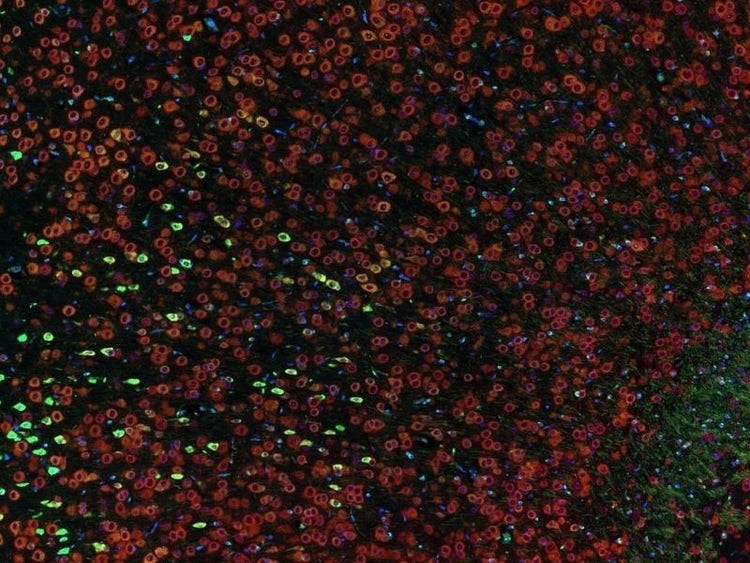

Fluorescence imaging of a mouse brain

각 확대 이미지는 특이해 보이지만, 모두 모아보면 형광 이미징으로 촬영한 생쥐 뇌가 나타납니다.

영국 과학자 George G. Stokes 경은 형석에 자외선을 비추면 형광을 발한다는 사실을 처음으로 목격했고, ‘형광’이라는 단어를 만들어냈습니다. Stokes 경은 형광 광원이 여기광원보다 파장이 더 길다는 사실을 발견했으며, 이 현상은 현재 스토크스 이동으로 알려져 있습니다. 형광 현미경은 자연적인 형태(일차 형광 또는 자가형광)이거나 형광을 발할 수 있는 화학물질로 처리했을 때 형광(이차 형광)을 발할 수 있는 물질을 연구하는 탁월한 방법입니다.